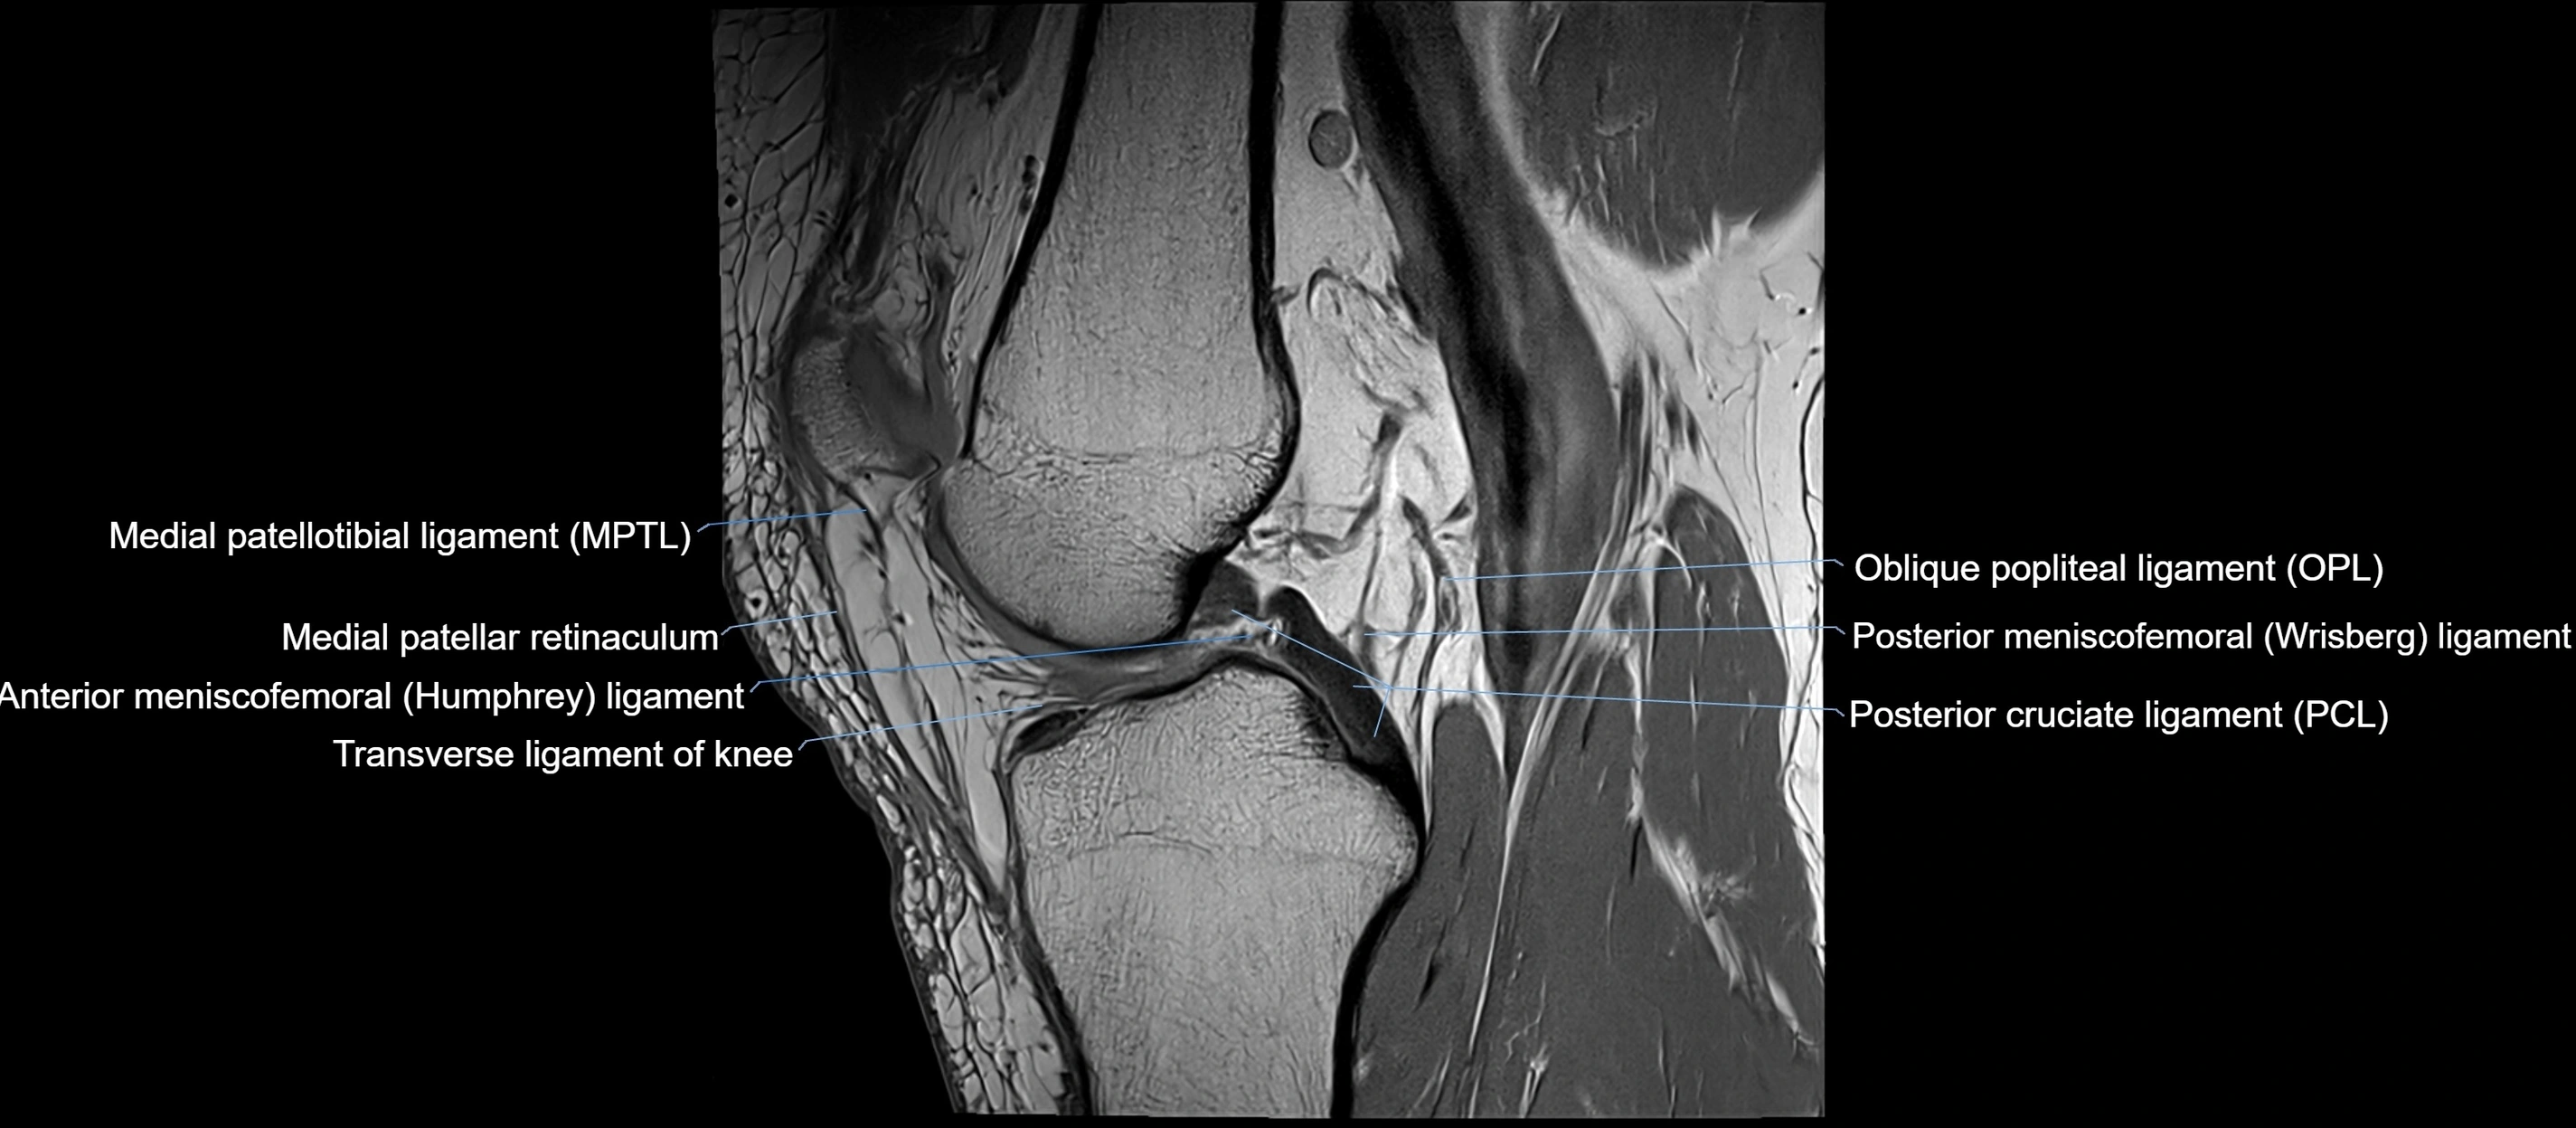

MRI images

image